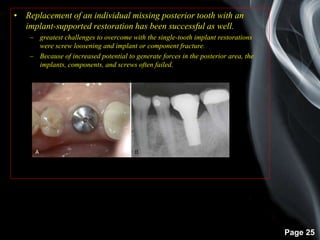

• Replacement of an individual missing posterior tooth with an

implant-supported restoration has been successful as well.

– greatest challenges to overcome with the single-tooth implant restorations

were screw loosening and implant or component fracture.

– Because of increased potential to generate forces in the posterior area, the

implants, components, and screws often failed.